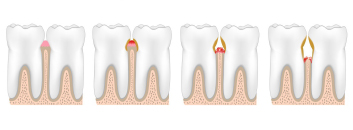

The stages of periodontal disease

Gingivitis

is the First stage and mildest form of periodontal disease. It causes the gums to become red, swollen, and bleed easily. Gingivitis is often caused by inadequate oral hygiene. Gingivitis is reversible with professional treatment and good oral home care.

Periodontitis

Untreated gingivitis can advance to periodontitis. With time, plaque can spread and grow below the gum line. The toxins stimulate a chronic inflammatory response in which the body in essence turns on itself and the tissues and bone that support the teeth are broken down and destroyed. Gums separate from the teeth, forming pockets (spaces between the teeth and gums) that become infected. As the disease progresses, the pockets deepen and more gum tissue and bone are destroyed.

Advanced periodontitis

As periodontitis advances, pockets deepen even more and can fill with pus. Around the roots of the teeth, the gums may start to swell. Bone loss continues. The teeth may feel sensitive to heat or cold and may hurt when brushed. Teeth loosen more. In some cases, teeth may need to be removed to keep the disease from spreading.